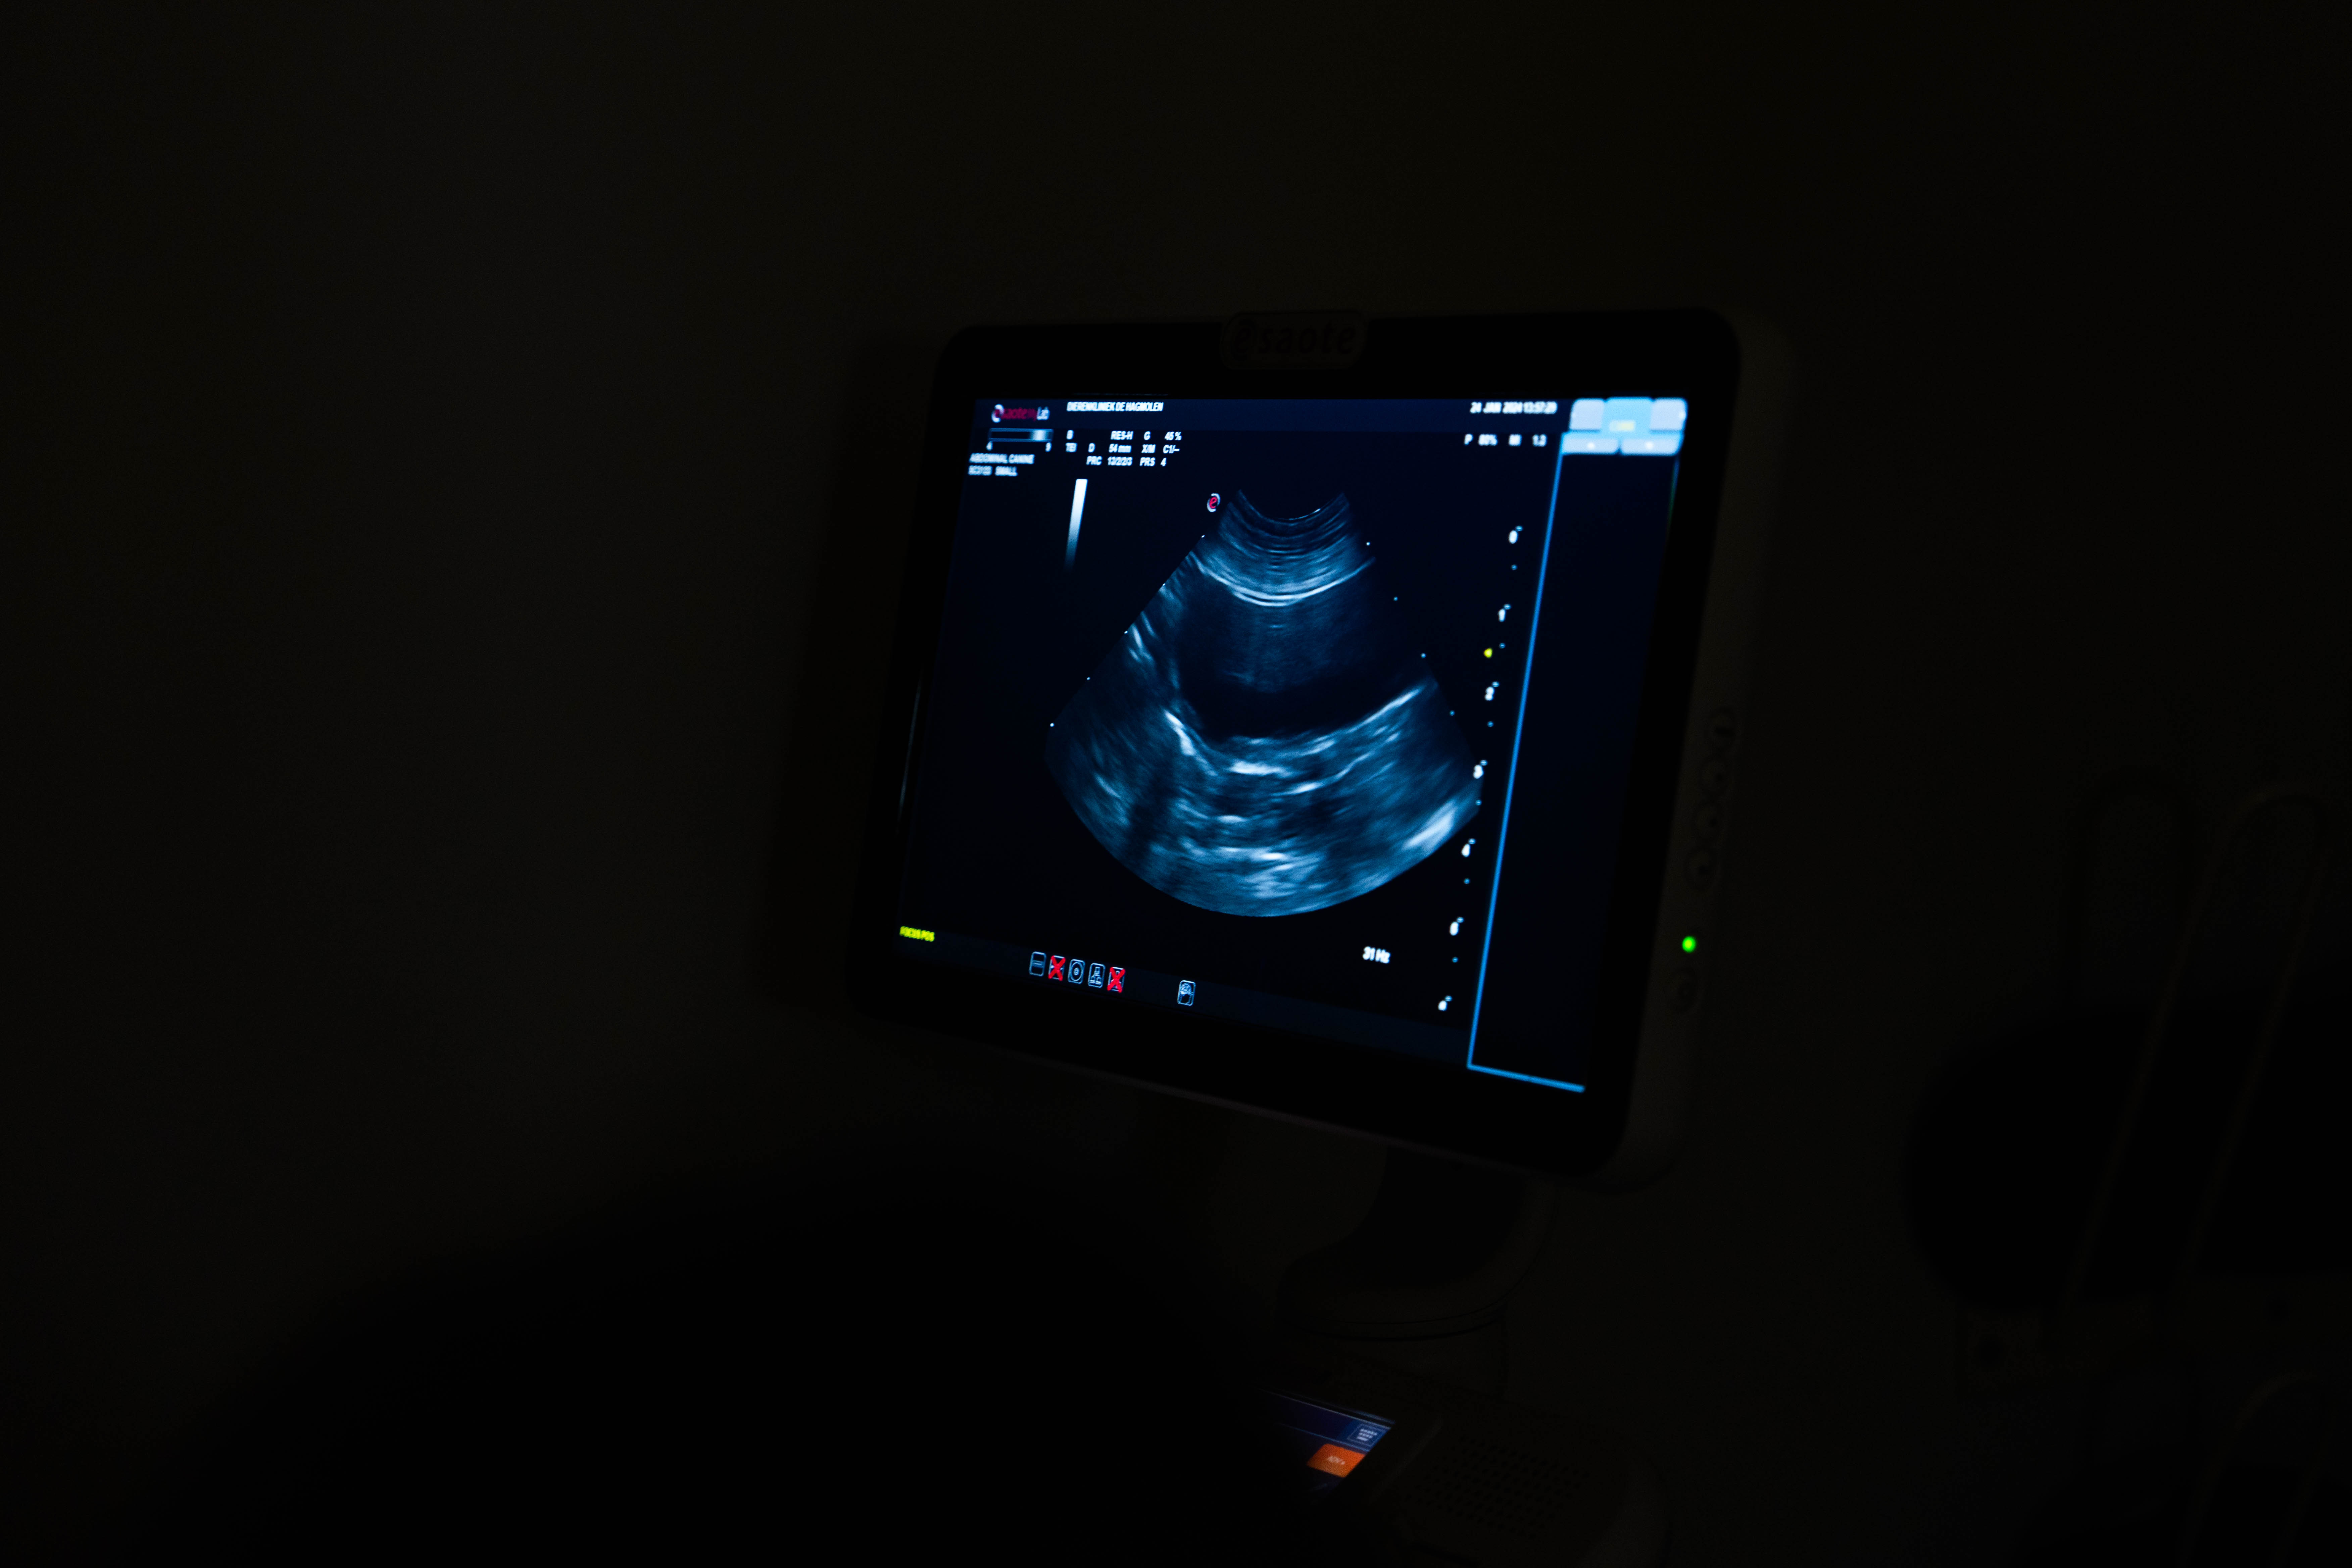

Om tot een juiste diagnose te komen zijn een goed kennisniveau en een gedegen klinisch onderzoek noodzakelijk. Daarnaast is het in veel gevallen nodig om aanvullend onderzoek te doen. Op onze kliniek hebben wij de mogelijkheid tot het verrichten van uitgebreid onderzoek.